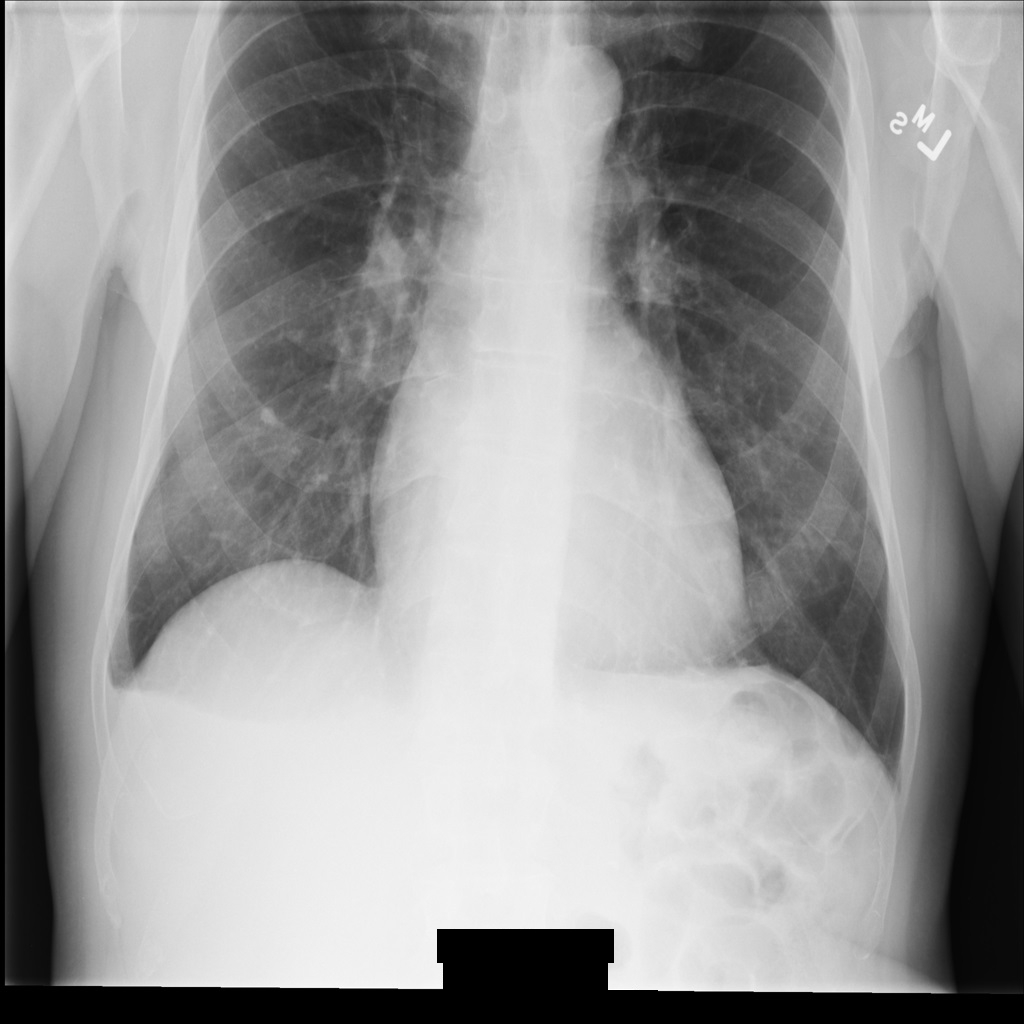

Après avoir anonymisé l'image à l'aide de REDACT_ALL_TEXT, elle se présente comme suit. Notez que tout le texte incrusté en bas de l'image a été masqué.

REDACT_ALL_TEXT.Masquer le texte sensible avec l'option "Nettoyer les descriptions"